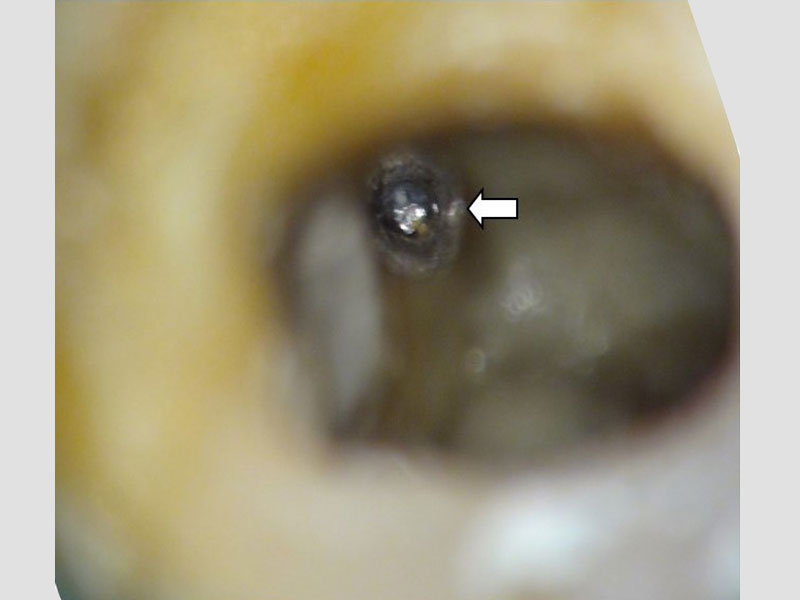

3. 拿出分離器械 (建議需在顯微鏡下、使用特殊器械)

圖例為案例分享:

分離器械移除B-1

分離器械移除B-2